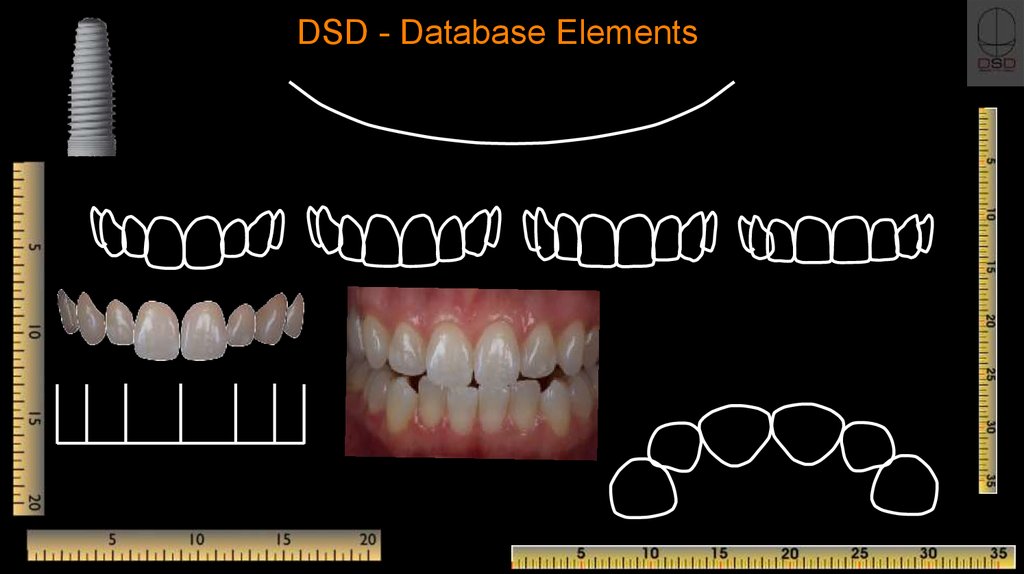

Digital Smile Design DSD Using Microsoft PowerPoint Full Protocol

DSD Digital Smile Design Online Presentation

Another Digital Smile Design Powerpoint Template you can download

- Implant CE Article Digital Smile Design In Implant Dentistry

- DSD Digital Smile Design Online Presentation